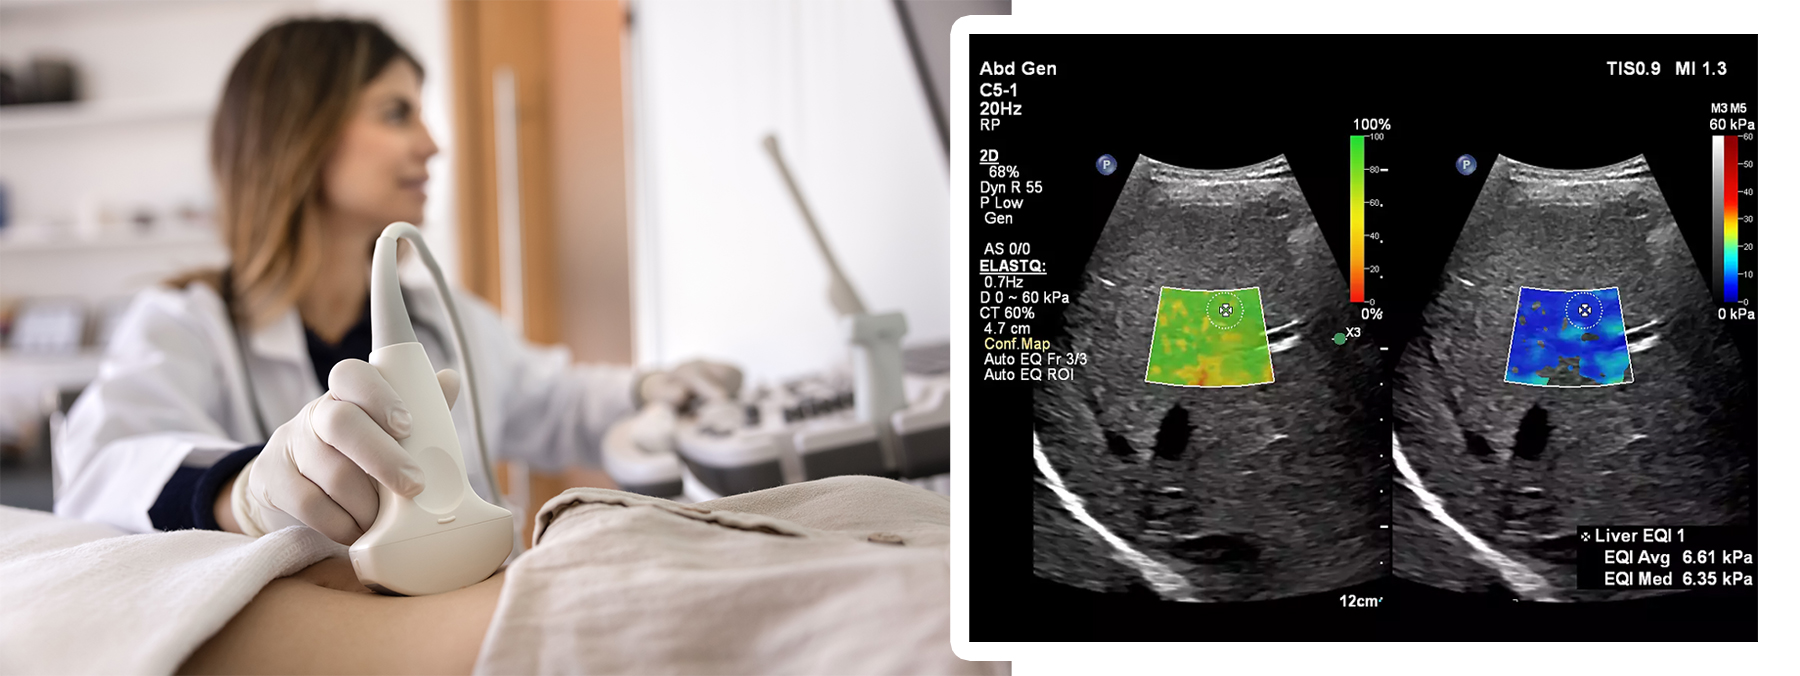

Zwanger-Pesiri Radiology’s advanced ultrasound department now offers Ultrasound Elastography of the Liver, an innovative, non-invasive way to assess liver health. This cutting-edge exam helps physicians evaluate liver stiffness, an important indicator of fibrosis or scarring, without the need for more invasive procedures. By combining traditional ultrasound imaging with advanced technology, patients benefit from a safer, faster, and more comfortable diagnostic experience.

Ultrasound Elastography works by using sound waves to measure how stiff or elastic the liver tissue is. During the exam, the ultrasound device sends gentle pulses through the liver. These pulses create shear waves that travel through the tissue, and the speed at which they move is measured. Stiffer liver tissue allows waves to travel faster, which can indicate fibrosis or other abnormalities. The results are then translated into quantitative data that physicians can use to evaluate liver health and guide treatment decisions.